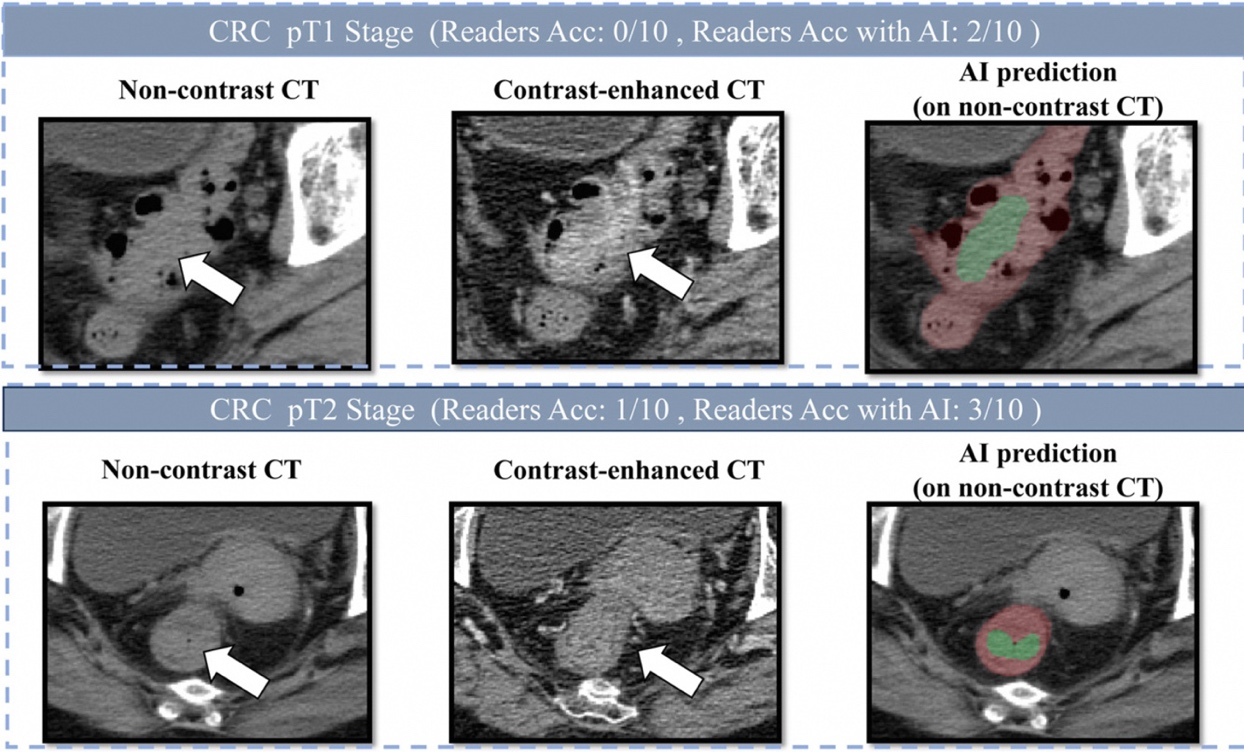

肠癌病灶在平扫CT、增强CT和AI画面上的表现

据研究团队发表在欧洲肿瘤内科学会官方期刊《肿瘤学年鉴》(Annals of Oncology,影响因子65.4)上的论文显示,DAMO COCA模型的敏感性(即防止漏诊的能力)达到86.6%,特异性更达到99.8%,即误诊率仅有0.2%。与10名不同年资的影像科医生相比,DAMO COCA模型的敏感性显著高出20.4%,在乙状结肠、直肠等易漏部位上的表现尤为突出。而在AI辅助下,医生的敏感性和特异性可分别提高14.5%和3.1%,有效减少临床漏诊。